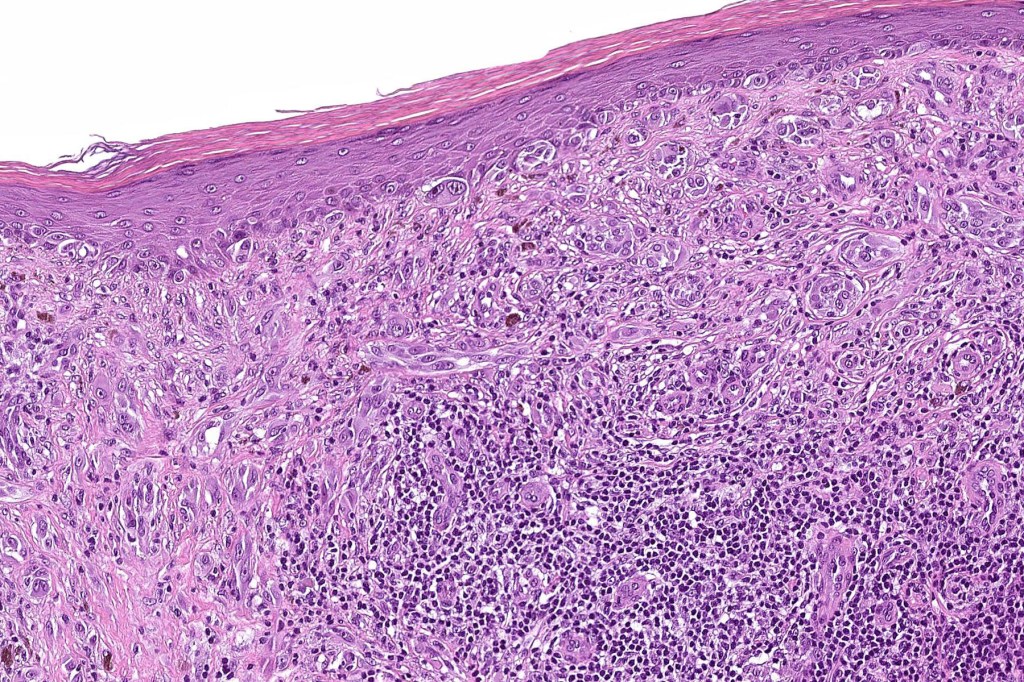

Histological features

•May show effacement/consumption of epidermis or ulceration

•Peripheral Pagetoid spread

•Large nodules which often show impaired maturation

•Loss of gradient with HMB45 and Ki67